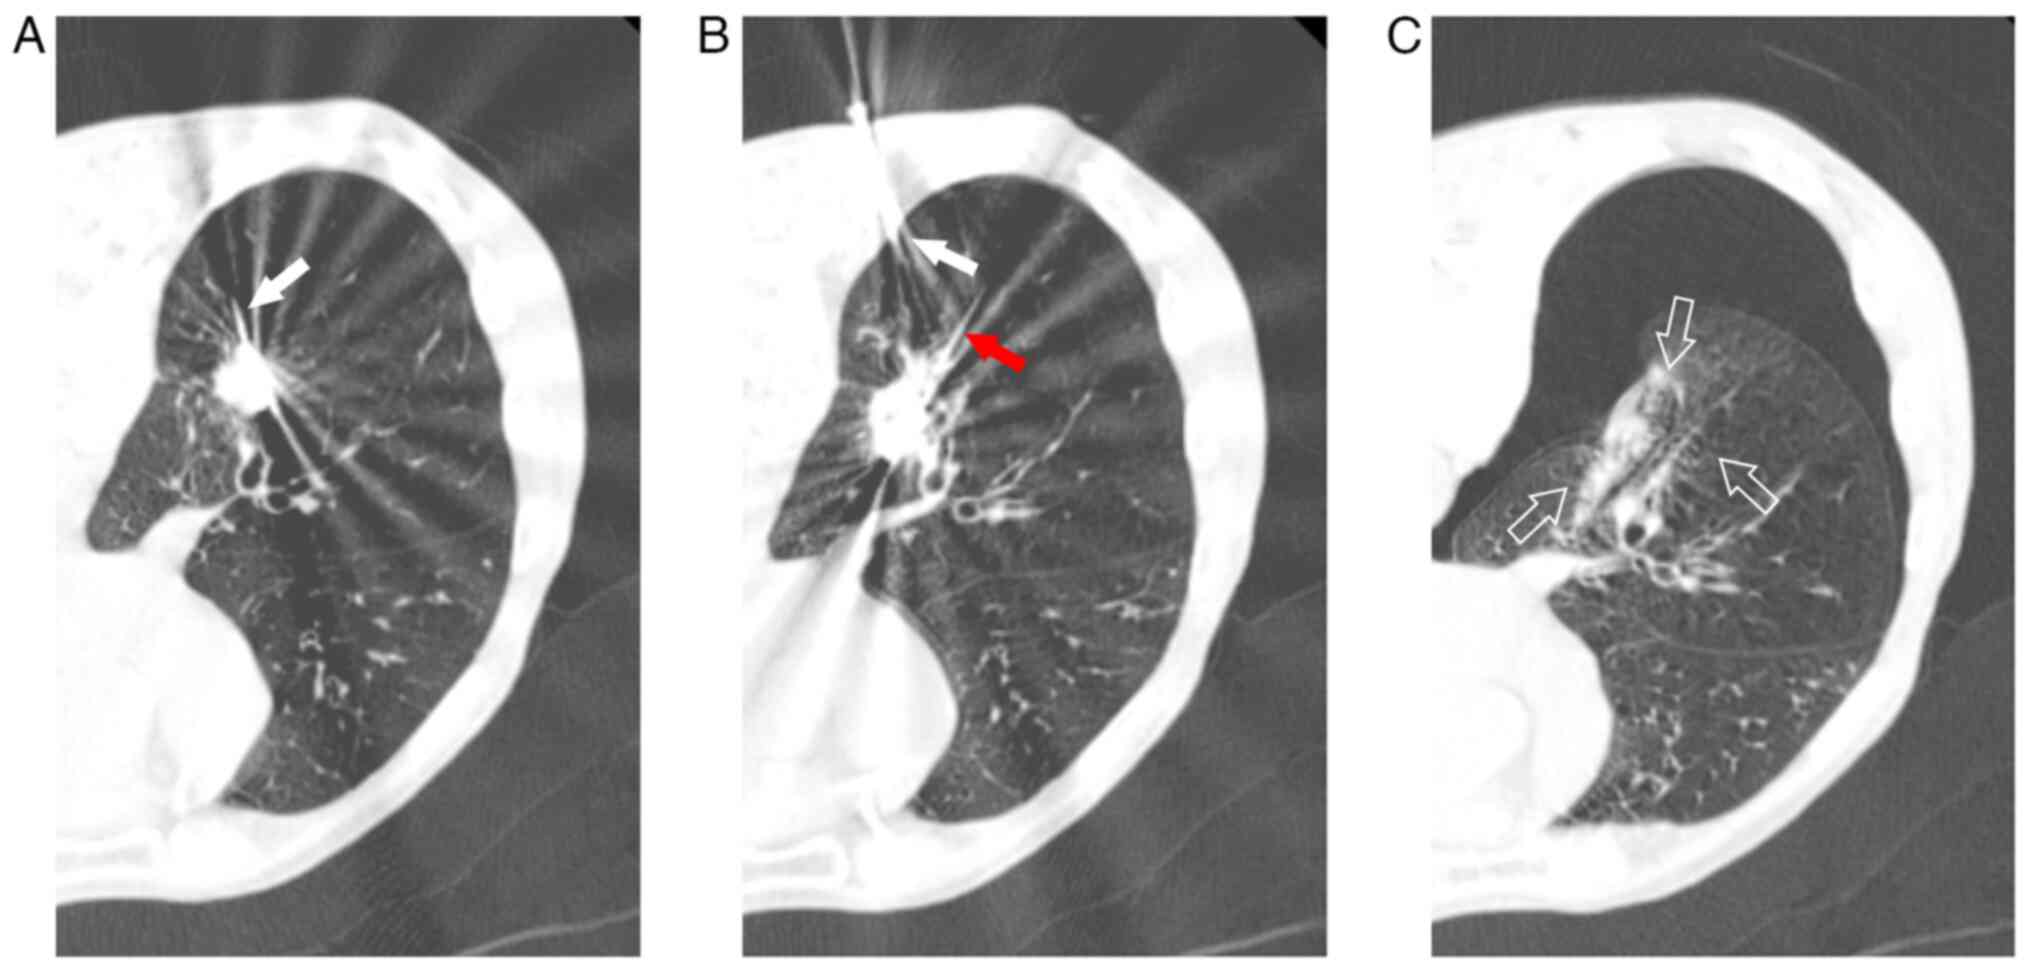

Prior to MWA, the patient received 100 mg pethidine intramuscularly. Subsequently, the patient was placed into the prone position and 1% lidocaine was injected locally into the pleural wall layer by layer. A total of two ECO-100al5 MWA needles were used, which were connected to the ECO-100a1 MWA system [ECO Medical Technology (Nanjing) Co., Ltd.]. The procedure involved a double-needle ablation approach, according to the manufacturer's guidelines (Fig. 3A and B). Needle 1 received 45 W radiation for 2 min, while needle 2 was treated with 45 W radiation for 2 min, followed by 50 W radiation for 3 min. A water circulation cooling system was used to maintain stable the surface temperature of the ablation needle. Prior to MWA, the revocation pathway was ablated, while immediate chest examination revealed right pneumothorax (Fig. 3C), necessitating closed thoracic drainage due to air bubbles observed during coughing. At six days following MWA, significant subcutaneous emphysema was detected in the neck and chest, with chest CT scan showing enlarged ablation and ground glass areas alongside a small pneumothorax with pleural effusion (Fig. 4A). By day 14, the patient experienced fever, cough with yellow purulent sputum, signs of pulmonary infection and encapsulated pleural effusion on chest CT scan (Fig. 4B). Therefore, the patient was administered ceftazidime (2.0 g twice daily) as an anti- microbial therapy. At 35 days after MWA, chest CT scan revealed encapsulated effusion in the right lower pleural cavity, gas-fluid flat and a 3-mm BPF in the posterior basal A subsegment bronchus (B10a) of the right lower lobe (Fig. 4C). Drainage was performed, while air bubbles and purulent fluid were observed during coughing and speaking. Pseudomonas aeruginosa was isolated from sputum and pleural effusion cultures. At 37 days following MWA, methylene blue was injected via bronchoscopy into the thoracic drainage tube. The results verified the presence of BPF (Fig. 5A and B), thus leading to the implantation of an EBV (EBV-TS-5.5; Pulmonx Corp.) in the right inferior lobe posterior basal segment bronchus (B10) at 45 days after MWA (Fig. 6A and B). EBV implantation markedly reduced air leakage, which was entirely stopped five days after implantation, thus allowing the removal of the thoracic drainage tube (Fig. 7A and B). Furthermore, at day 86 after EBV implantation, chest CT scan revealed that the pulmonary infection and narrowed pulmonary necrotic cavity had resolved (Fig. 7C and D; Table I). No serious complications were recorded at 6-month follow-up.

CT images showing the tumor in the right lower pulmonary lobe during MWA. (A) A single-point ablation was performed in the upper part of the tumor and (B) another one in the lower part of the tumor. The white and red arrows point to needle 1 and needle 2, respectively. (C) Chest CT scan showed pneumothorax following MWA. The empty arrows indicate the ground glass area of ablation. CT, computed tomography; MWA, microwave ablation.

Figure 5

Bronchoscopy was performed at 37 days after microwave ablation. (A) The posterior basal segment bronchus of the right lower lobe. (B) After methylene blue was injected into the thoracic drainage tube, bronchoscopy showed blue fluid gushing from the posterior basal segment bronchus of the right lower lobe.